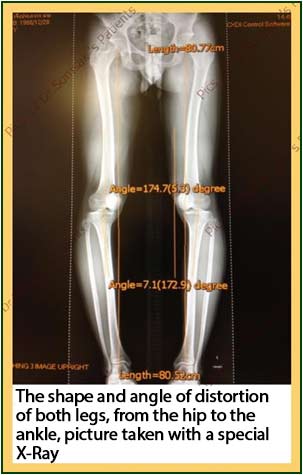

“The operation to straighten both knees at the same time with the new MHTO Method”

Modified High Tibial Osteotomy with Charnley Clamp technique can be used to correct bowlegs on both sides at once.